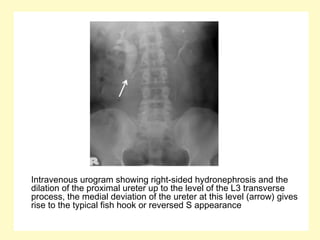

Intravenous urogram showing right-sided hydronephrosis and the

dilation of the proximal ureter up to the level of the L3 transverse

process, the medial deviation of the ureter at this level (arrow) gives

rise to the typical fish hook or reversed S appearance